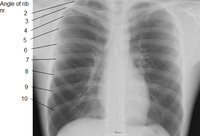

The rib cage is an arrangement of bones in the thorax of all vertebrates except the lamprey and the frog. It is formed by the vertebral column, ribs, and sternum and encloses the heart and lungs. In humans, the rib cage, also known as the thoracic cage, is a bony and cartilaginous structure which surrounds the thoracic cavity and supports the pectoral girdle (shoulder girdle), forming a core portion of the human skeleton. A typical human rib cage consists of 24 ribs, the sternum (with xiphoid process), costal cartilages, and the 12 thoracic vertebrae. Together with the skin and associated fascia and muscles, the rib cage makes up the thoracic wall and provides attachments for the muscles of the neck, thorax, upper abdomen, and back.